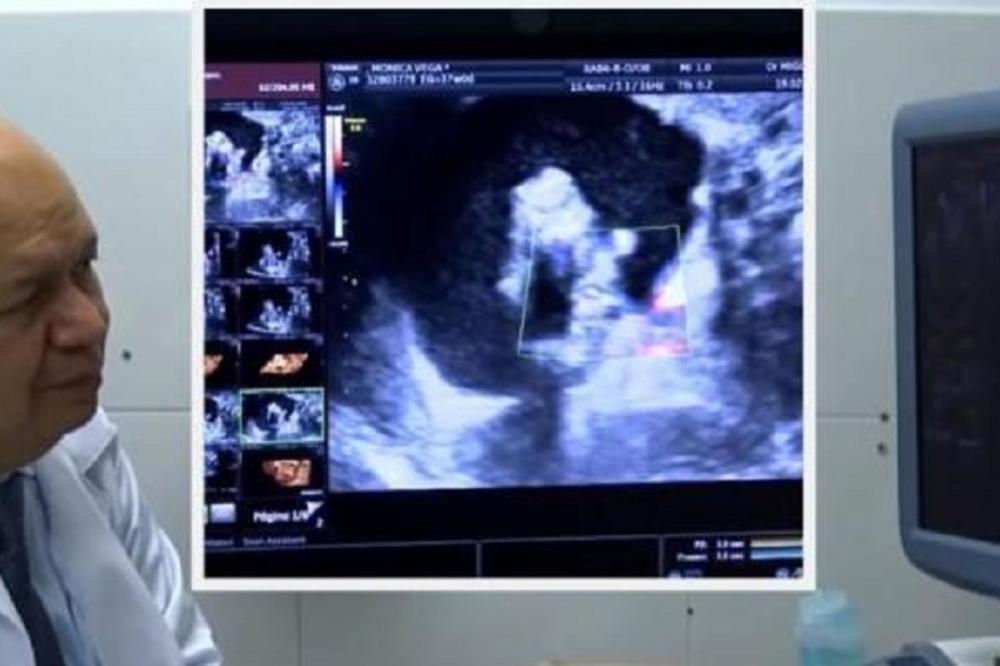

U telu malene Icamare rasla je njena sestra bliznakinja, a lekar je to uočio tokom ultrazvuka, dok je devojčica još bila u stomaku svoje majke Monike Vege (33).

Opstetričar, koji je Moniku poslao kod dr. Migela Para-Savedra, mislio je da nerođena beba ima nekakvu cistu, ali prevario se. Bilo je to sićušno, napola razvijeno telo bez srca i mozga u bebinom abdomenu, nešto što se događa vrlo retko, otprilike u jednom naspram pola milionaa rođenja. Majku Moniku je dr. Para-Savedra prvi put video kada je bila u 35. nedelji trudnoće.

Odmah ju je pregledao kolor doplerom i 3D/4D ultrazvučnim snimanjem. Ono što je video šokiralo ga je. U bebi je video prostor ispunjen tečnošću u kojoj je bilo minijaturno dete. Ono se zasebnom pupčanom vrpcom opskrbljivalo krvlju, a pupčana vrpca završavala je na crevu većeg blizanca, tj, malene Icamare.